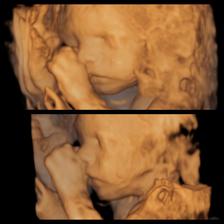

15.07.2016 : morfologický ultrazvuk Martin, MUDr. Grochal (28tt+4)